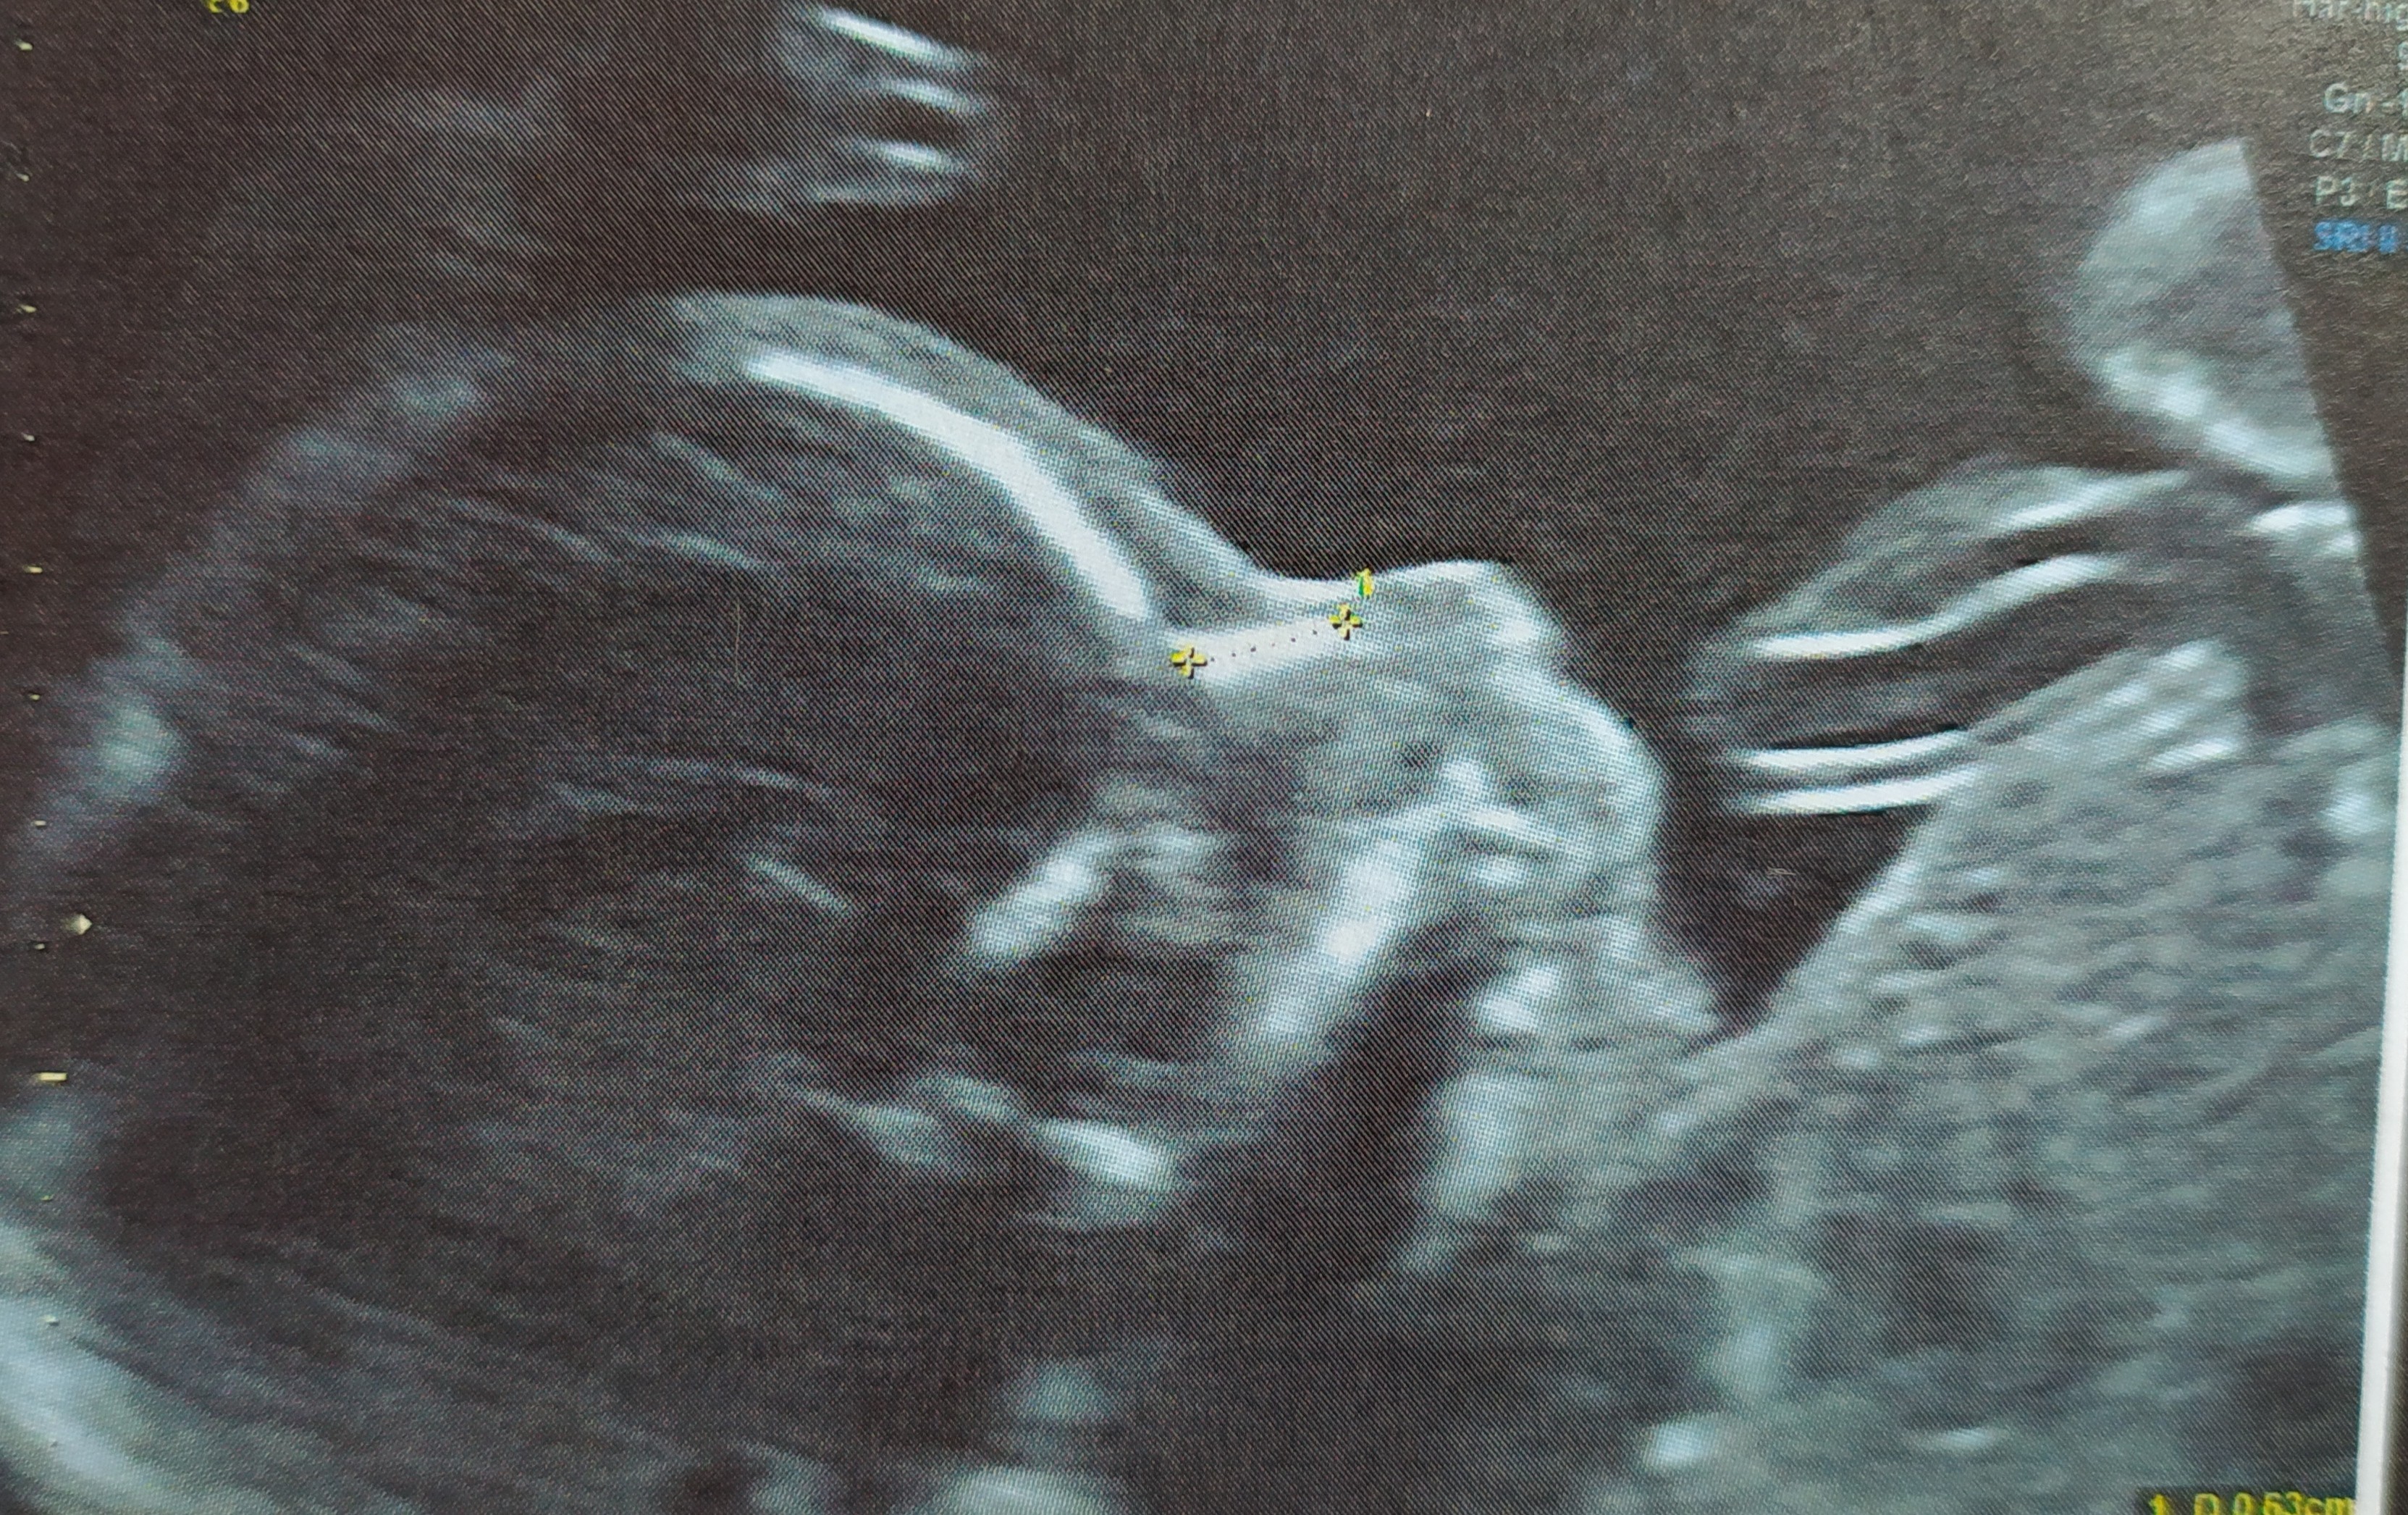

Też byłam zdziwiona, ale chyba najbardziej że będę miała 3 dziewczynkę. Byłam przekonana że będzie wymarzony syn, inaczej się czułam inne zachcianki niż w ciążach z córkami, rodzina mówiła że na pewno syn itd jak mój mąż miał ur to też mu tego syna życzyli, córki też bardzo brata chciały, a jak zobaczymy balon z różowym konfetti były bardzo zawiedzione, normalnie przepłakałam 2dni nie umiałam się pozbierać, mąż wspierał i mówił czy córka czy syn co za różnica ważne że zdrowe. Dziś już jest na szczęście ok ale dalej się tak dziwnie czuję. Wiem glupia jestem zamiast się cieszyć że zdrowe to ja załamka. A oto zdjęcie naszej małej teraz problem z imieniem chyba je nadamy jak się urodzi.

Załączniki

• IMG_20201130_142229.jpg

IMG_20201130_142229.jpg

2 MB · Wyświetleń: 93